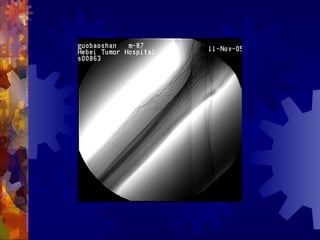

糖尿病足的检查

4. 足部 X- 线检查

5. 动脉造影(下肢)